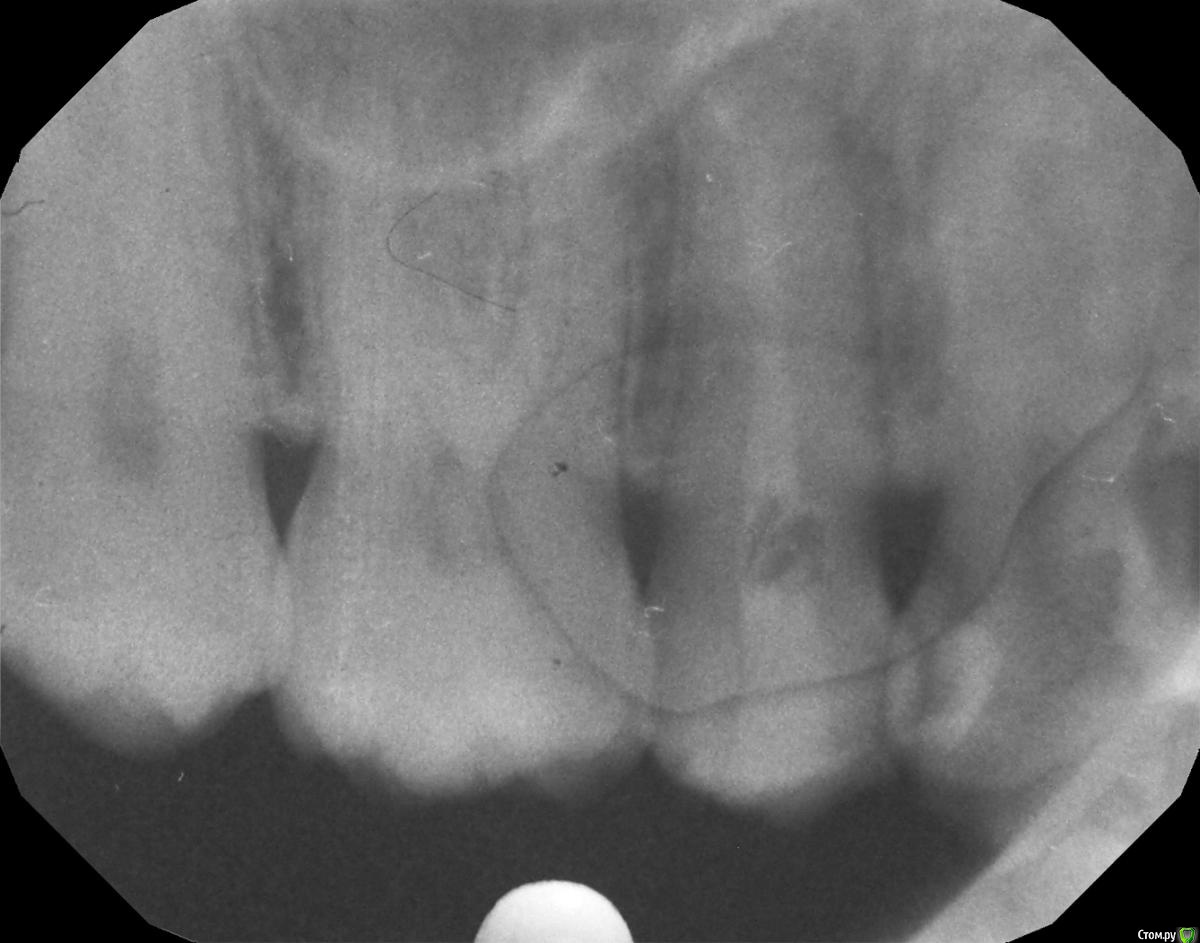

Гарриевич Опубликовано 21 сентября, 2015 Поделиться Опубликовано 21 сентября, 2015 кроме горячего и зубной нити на что то еще реагирует?в зубе сделан достаточно глубокий ложный ход, покажите все снимки начиная с первого Ссылка на комментарий

hichi Опубликовано 25 сентября, 2015 Автор Поделиться Опубликовано 25 сентября, 2015 (изменено) в зубе сделан достаточно глубокий ложный ход это "пробурили" когда искали дополнительный канал, после того как заболел от горячего. Док говорит что там нормально все перфорации нет. Изменено 25 сентября, 2015 пользователем hichi Ссылка на комментарий

hichi Опубликовано 25 сентября, 2015 Автор Поделиться Опубликовано 25 сентября, 2015 (изменено) покажите все снимки начиная с первого Гарриевич сказал(а) 22 Сен 2015 - 00:35: покажите все снимки начиная с первого + 1 пожалуйста первичное эндо когда заболел от горячего искали доп. анатомию кальций с ложным ходом есть только один снимок, который в самом первом сообщенииесть еще один через 3 мес после лечения но он не совсем удачно сделан, думаю ничем вам не поможет Изменено 25 сентября, 2015 пользователем hichi Ссылка на комментарий